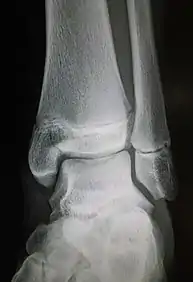

Fracture of the lateral malleolus seen on X-ray scan (left ankle)

The Maisonneuve fracture generally follows a specific pattern of injury. The following are described as subsequent events that result in a Maisonneuve fracture:[3][4][12]

• Forceful, external rotation of the ankle joint results in the tearing of the deep deltoid ligament and/or an avulsion fracture of the medial malleolus.

• The ankle mortise is subjected to excessive torque, rupturing the syndesmotic ligaments and anteromedial ankle joint capsule.

• Rotative energy is transferred upwards along the interosseous membrane, damaging it in the process.

• The force results in a spiral, sometimes an oblique, fracture at the neck of the proximal fibula.

In cases where the anterior aspect of the tibiofibular syndesmosis can resist mechanical stress, only an oblique fracture of the lateral malleolus is produced. Diastasis of the lateral malleolus may also occur, in which it is posterolaterally displaced from the tibia.[9]